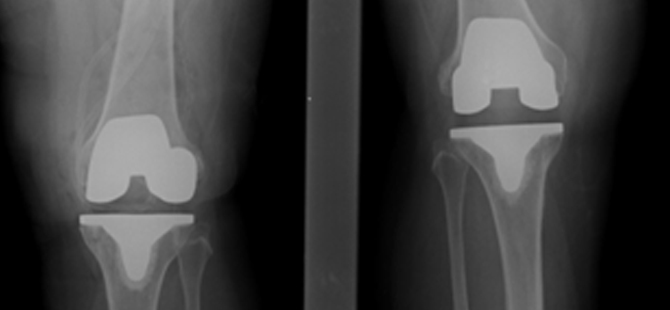

Bi-lateral Total Knee Replacement performed successfully at MIOT

Finally in Feb 2014 they came to MIOT and consulted with the Knee Replacement surgeon. After the investigations, the Doctor advised them surgery. As her Right Knee condition was worse than her left, they decided to operate her right initially followed by her left after 6months. She was taken up for Total Knee Replacement surgery of Right knee on 19th Feb 2014.

From the next day she was advised active Physiotherapy and in 7 days time, she was discharged. In 2 weeks time, she had no pain in her right knee and was able to put weight on that leg and walk. In August 2014, with full confidence that she will walk freely post surgery, she was taken up for Total Knee Replacement surgery of left knee.